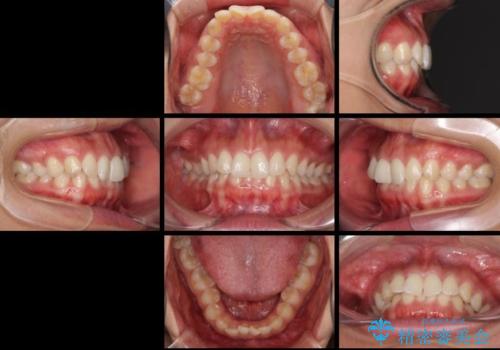

- 深い咬み合わせ(ディープバイト)と前歯のデコボコを気にして来院された患者様です。

インビザラインによる上下歯列の側方拡大と後方移動、IPR(歯と歯の間を削る)にるスペースの獲得により、デコボコとディープバイトを改善することとしました。

後方移動に際し、下顎の親知らずは2本とも抜歯することとしました。

1日22時間の装着時間をしっかり守ってくださったので、予定通り1年で治療を終えることができました。

ディープバイトによる食いしばり癖も解消され、患者様には大変満足していただきました。